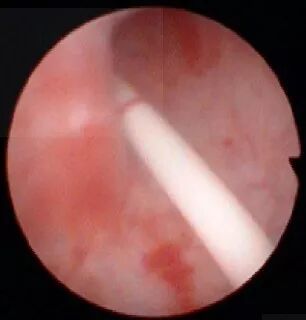

图 1. 挑起输尿管上唇

(1)顺导丝将输尿管镜推至输尿管口,把目镜抬高 30°~60°并轻轻持续用力推进,然后把输尿管镜慢慢压平,挑起输尿管上唇,常可顺利进入,同时会感到有突破感。

(2)顺导丝将输尿管镜推至输尿管口后,如为左侧输尿管则顺时针旋转镜体 90°并外展输尿管镜目镜,缓慢持续轻轻用力推进,同时把镜体慢慢内收,挑起输尿管外侧壁,常可顺利进入,同时也会感到有突破感;如为右侧输尿管则逆时针旋转 90°并外展输尿管镜目镜。